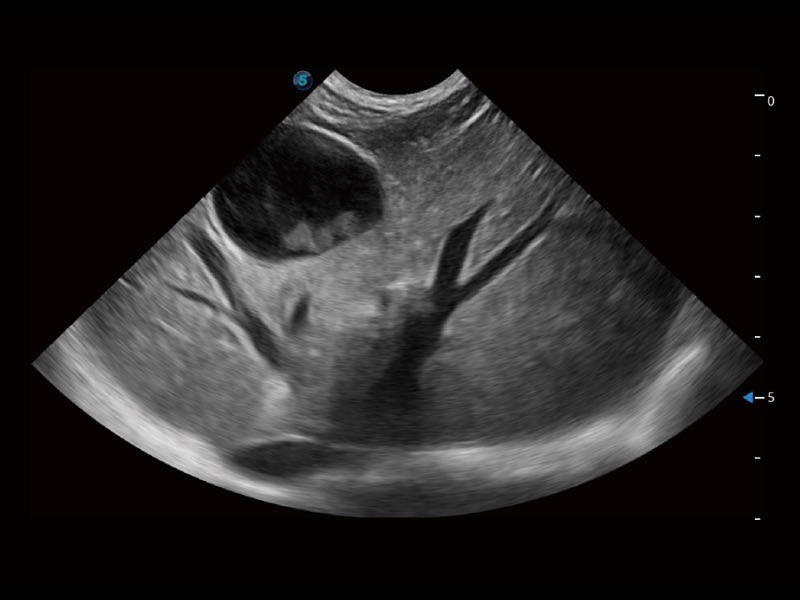

动物是人类最亲密的朋友和最值得信赖的伙伴。竞技宝(JJB)官方网站也一直致力于探索动物专用的超声影像解决方案。全新推出的ProPet系列,是竞技宝(JJB)官方网站在动物超声影像智能化、专业化、精准化的一次跨越式革新。动物不能用言语来表述自己的不适,通过超声影像,ProPet系列搭建了动物医生与不同物种沟通的“桥梁”,为动物医生注入了“治愈之力”。 ProPet 70将是您值得信赖的超声伙伴。它配备了复合材料线阵探头,帮助动物医生获得卓越精准的临床图像。同时ProPet 70直观便捷的操作体验以及专业的测量工具,可为不同体型和生理结构的动物带来全面临床评估,切实为动物医生提供智能、专业、精准的超声影像解决方案。

ProPet 70 进一步提升了微米成像算法,更加注重对基础原始图像的还原和保留,在有效减少斑点噪声、增强组织边界显示的同时,避免过度优化丟失真实的解剖信息。

ProPet 70专为动物医生设计,对不同的动物体型和生理结构作出了针对性的优化。通过动物影像专用软件,可满足个性化的应用需求,帮助动物医生获得更精确的诊断数据。

ProPet 70 全新的动物超声智能软件和丰富的探头群,为动物医生提供了高清晰度和精细分辨率的图像,无论在宠物、马科、畜牧还是实验室动物等应用中都可以轻松应对,为您的日常工作带来满意的体验。